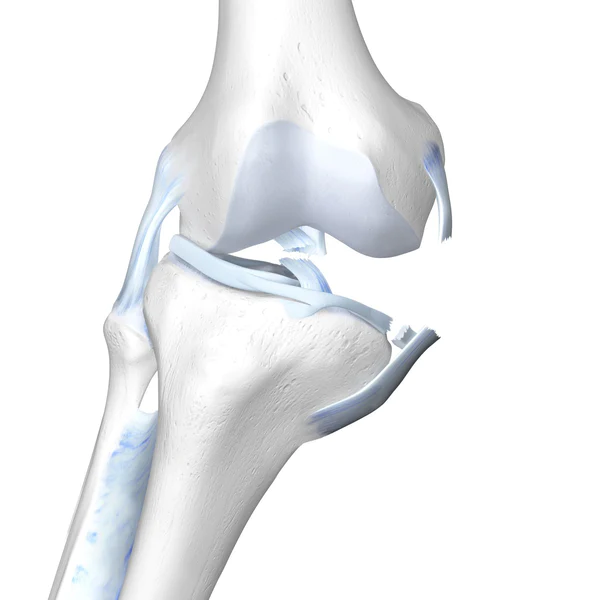

관절은 우리 몸의 운동 범위를 안전하고 넓게 가동할 수 있는 역할을 하게 됩니다. 이러한 관절 중에 팔의 중심부인 팔꿈치와 다리의 중심부인 무릎의 경우에는 여러 인대와 근육, 기타 구조물 들이 위치하고 있습니다. 무릎이 Lateral 에서 Medial 로 큰 충격을 받게 되면(Valgus force) 내측에 있는 구조물 들이 영향을 받게 되는데 아래 그림과 같은 매커니즘으로 손상을 입게 됩니다.

손상 규모가 큰 경우에는 다른 외상에 비해 치료할 부위가 많아지게 됩니다. (팔꿈치의 경우 terrible triad 에서 elbow dislocation 과 매칭하여 무릎은 팔꿈치보다는 안정된 구조물로 ACL tear 를 기준으로 보면 쉽게 이해할 수 있을 것 같습니다.)